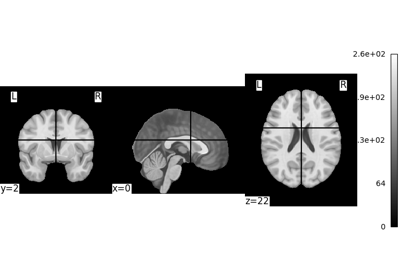

Exercise: Varying the amount of smoothing in an image

Compute the mean EPI for one individual of the brain development dataset downloaded with nilearn.datasets.fetch_development_fmri and smooth it with an FWHM varying from 0mm to 20mm in increments of 5mm

Intermediate steps:

1. Run nilearn.datasets.fetch_development_fmri and inspect the .keys() of the returned object

2. Check the nilearn.image module in the documentation to find a function to compute the mean of a 4D image

3. Check the nilearn.image module again to find a function which smoothes images

4. Plot the computed image for each smoothing value

A solution can be found here.